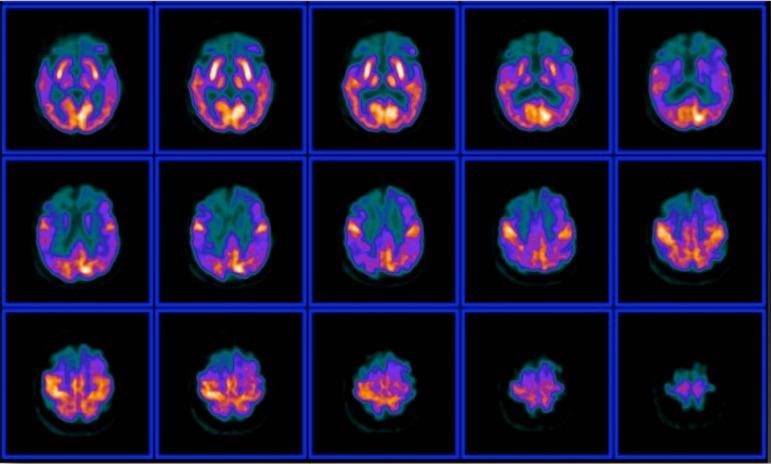

阿尔茨海默病的多模态成像方法。第二部分:氢质子磁共振波谱、氟代脱氧葡萄糖正电子发射断层显像和淀粉样蛋白正电子发射断层显像

Multimodality Imaging Approaches in Alzheimer's disease. Part II: 1H MR spectroscopy, FDG PET and Amyloid PET.

In this Part II review, as a complement to the Part I published in this supplement, the authors cover the imaging techniques that evaluates the Alzheimer's disease according to the different metabolic and molecular profiles. In this section MR spectroscopy, FDG-PET and amyloid PET are deeply discussed.

摘要

在本第二部分综述中,作为对本增刊第一部分的补充,作者介绍了根据不同代谢和分子特征评估阿尔茨海默病的成像技术。在本节中,将深入讨论磁共振波谱、氟代脱氧葡萄糖正电子发射断层显像(FDG-PET)和淀粉样蛋白正电子发射断层显像(amyloid PET)。